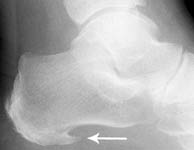

Taudin riskiä lisäävät myös keski-ikä ja ylipaino. 70 prosentille kehittyy jänteen kiinnityskohtaan luupiikki, joka

näkyy röntgenkuvassa kantaluun kärjessä piikkimäisenä luuna osoittaen kantapohjasta varpaisiin päin. Ulospäin

Luupiikkejä diagnosoidaan röntgen-, ultraääni-, CT- ja magneettikuvilla.